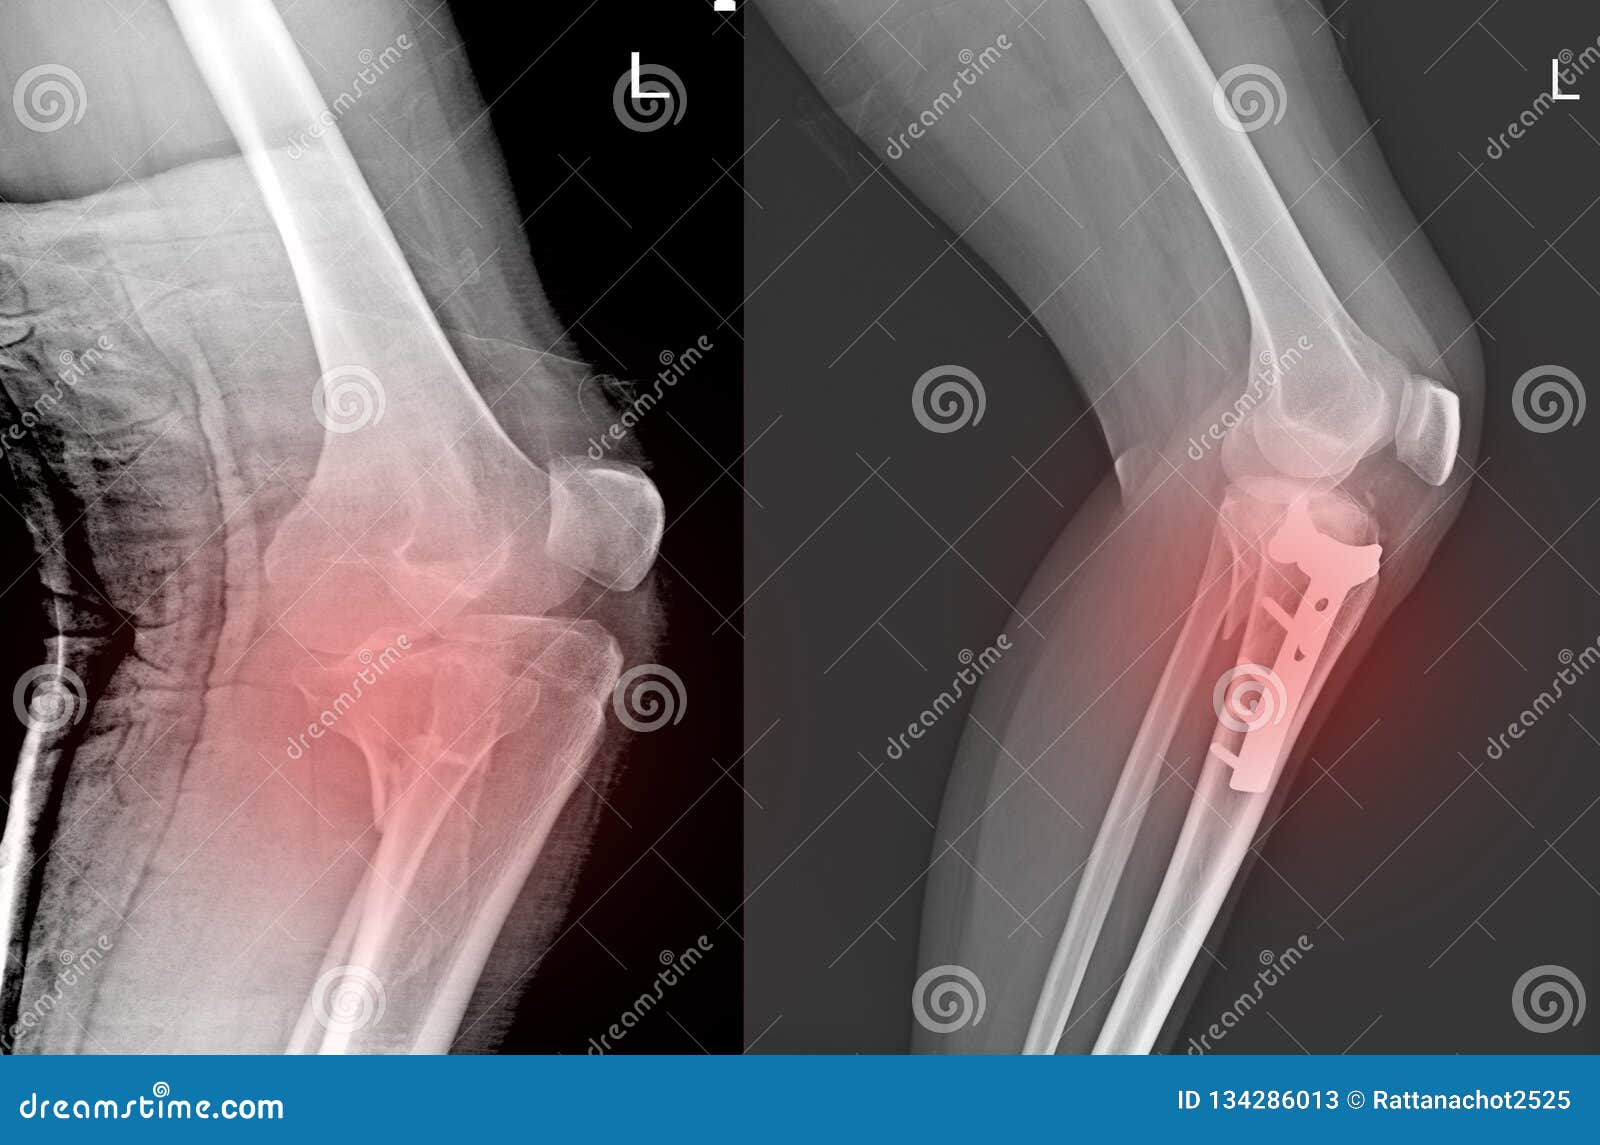

В травматологии приятно считать, что смещение отломков более чем на три миллиметра, и/или наличие ступенек на суставной поверхности высотой более 2 миллиметров требует операции, в ходе которой отломки сопоставляют, восстанавливают суставную поверхность и фиксируют надколенник (выполняют остеосинтез).

Как фиксируют надколенник? Вариант остеосинтеза определяется типом перелома. При поперечном переломе сопоставить и скрепить отломки можно с посощью специальной медицинской проволоки (серкляжа) и спиц. Такую операцию называют именем ее изобретателя – Вебера.

Иногда отломки успешно скрепляются винтами, или винтами и проволокой.

При многооскольчатом переломе также нужно использовать винты и проволоку, которыми скрепляют отломки друг с другом.

Лечение переломов

Лечение перелома надколенника зависит от смещения отломков. При переломе без смещения возможно лечение гипсовой повязкой, при малейшем смещении — необходима операция на коленной чашечке. Смещение отломков составной поверхности надколенника должно быть обязательно устранено на операции, поскольку именно суставная поверхность надколенника скользит по мыщелкам бедренной кости при разгибании ноги в коленном суставе. При наличии смещения либо будет вообще отсутствовать разгибание, либо будет формироваться артроз бедренно-надколенникового сочленения. Отломки при переломе надколенника можно фиксировать винтами, спицами, проволокой.

При наличии смещения либо будет вообще отсутствовать разгибание, либо будет формироваться артроз бедренно-надколенникового сочленения. Отломки при переломе надколенника можно фиксировать винтами, спицами, проволокой.

Фиксация перелома надколенника винтами.

Наиболее распространённый способ фиксации – это остеосинтез по Веберу, хирургу, который придумал эту операцию. При этой операции для фиксации используются спицы и проволока (продемонстрировано на схеме ниже).

Рентгенограммы после остеосинтеза надколенника по Веберу.

После операции на надколеннике коленный сустав обездвиживают гипсом или ортезом.